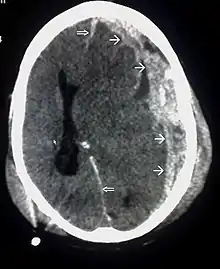

CT scan showing cerebral contusions, hemorrhage within the hemispheres, and subdural hematoma. There is also displaced skull fracture of left transverse parietal and temporal bones.[2]

CT scan showing spread of the subdural hematoma (single arrows), midline shift (double arrows)

Systems also exist to classify TBI by its pathological features.[20] Lesions can be extra-axial, (occurring within the skull but outside of the brain) or intra-axial (occurring within the brain tissue).[24] Damage from TBI can be focal or diffuse, confined to specific areas or distributed in a more general manner, respectively.[25] However, it is common for both types of injury to exist in a given case.[25]

Hematomas, also focal lesions, are collections of blood in or around the brain that can result from hemorrhage.[11] Intracerebral hemorrhage, with bleeding in the brain tissue itself, is an intra-axial lesion. Extra-axial lesions include epidural hematoma, subdural hematoma, subarachnoid hemorrhage, and intraventricular hemorrhage.[38] Epidural hematoma involves bleeding into the area between the skull and the dura mater, the outermost of the three membranes surrounding the brain.[11] In subdural hematoma, bleeding occurs between the dura and the arachnoid mater.[23] Subarachnoid hemorrhage involves bleeding into the space between the arachnoid membrane and the pia mater.[23] Intraventricular hemorrhage occurs when there is bleeding in the ventricles.[38]